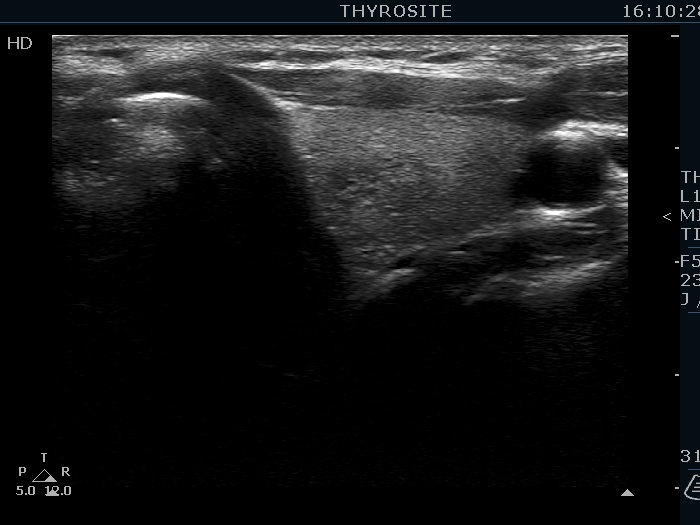

Ultrasonography. The thyroid was echonormal. There were several hypoechoic nodules in the left lobe. The middle one had back wall cystic figures. There were 3 or four discrete, deeply hypoechoic lesions above and lateral to the left lobe in the neck. One of them presented with a hilum-like figure while the others lacked hilum.